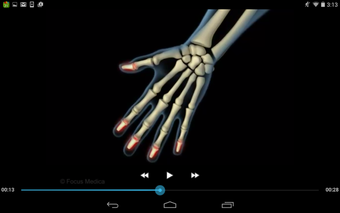

该应用程序是一本包含100个与风湿病相关的术语和定义的词典。定义以简单易用的格式呈现,辅以3D动画和视频。该应用程序分为两个部分:第一部分与医疗状况有关,第二部分与治疗和用于治疗状况的药物有关。

该应用程序是一本包含100个与风湿病相关的术语和定义的词典。定义以简单易用的格式呈现,辅以3D动画和视频。该应用程序分为两个部分:第一部分与医疗状况有关,第二部分与治疗和用于治疗状况的药物有关。